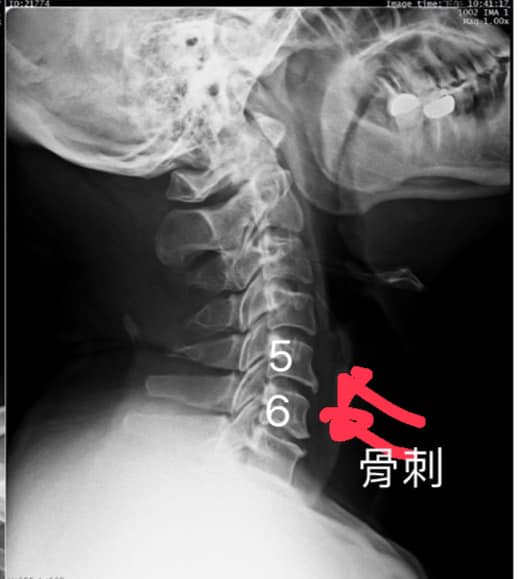

「徐醫師!我的肩膀痛到沒有辦法睡覺!到底是什麼回事???」楊先生痛苦的詢問我,看了一下他帶過來的C光片發現他的第五第六頸椎前緣骨頭都變形,在按壓一下頸椎關節面的地方他異常疼痛!他敘述在按壓這些關節面的時候手還會麻。

❇️診斷:C4/C5/C6壓迫神經根